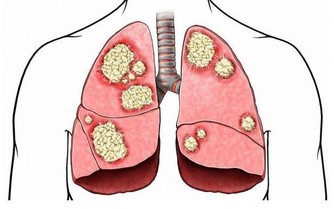

心臟病是全世界的頭號死亡原因,所以任何人都要了解它的風險性,

特別是如果你患有2型糖尿病,尤其如果你是女性。

因為,患有糖尿病的成年人死於心臟病的可能性,是沒有心臟病的成年人的兩到四倍。

了解心臟病與糖尿病之間的聯繫,才能有助於幫你減少一些風險。